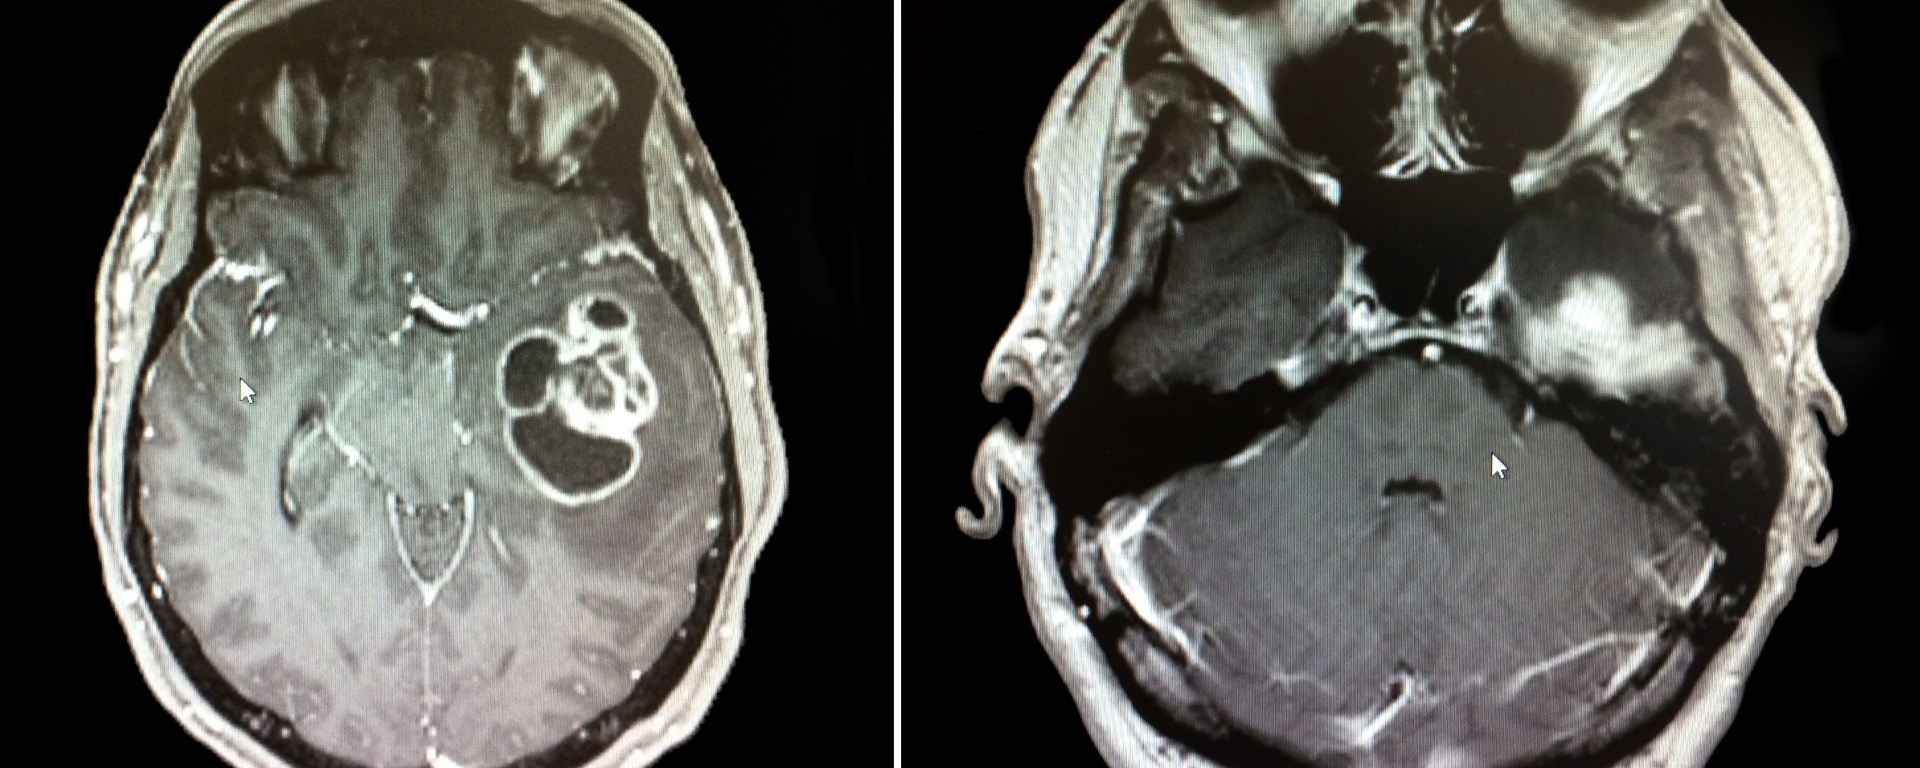

Three dimensional culture systems and patient derived cells successfully allow for tumoroid development. Tumoroids are structures that grow and appear morphologically similar to naturally growing tumors in a patient. Tumoroids show promise for testing new drugs and cancer treatments. For instance, glioblastoma is a form of brain cancer that is aggressive, fast growing, and deadly. In particular, the mesenchymal subtype of this cancer shows more proliferative growth in a faster period of time. To better understand the tumoroid development, Dr. Lisa Oliver and her research team have created a 3D cell culture model, which mimics the environment in which glioblastoma and mesenchymal tumor cells grow.

To mimic the tumor microenvironment found in the brain, a co-cell culture was made using patient derived cells and bone marrow mesenchymal stem cells. A co-culture refers to a cell culture that contains two or more types of cells. The patient derived cells were collected from patients that were undergoing glioblastoma tumor removal surgery. The stem cells were collected from a French tumor library. The cell viability, cell proliferation, and percentage of tumor-initiating cells was analysed for the growing tumoroids. The morphology of the tumoroids, such as their length, area, and circularity, were analyzed. Additionally, radiation and chemotherapy were used on these tumoroids to determine their survival and cell proliferation probabilities.

The researchers noticed that patient derived cells began to create multicellular spheroids within seven days of being placed in the co-culture. It was inferred that the tumoroids responded to radiation methods, as there was a decrease in the number of cells in the culture. In addition, the morphology and behavior of the lab-grown tumors exhibited similar characteristics to patient-related glioblastoma and mesenchymal tumors.